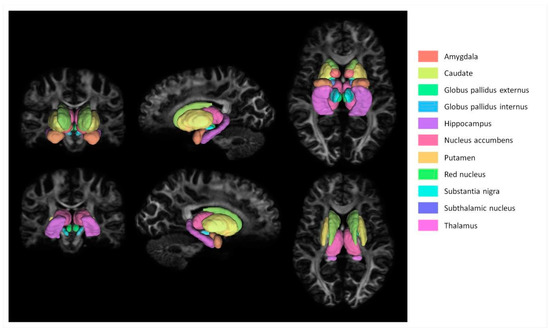

2. Materials and Methods

2.3. Image Processing